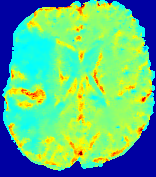

Figure 3: PIANO feature maps for one stroke patient, where the lesion is located in the left hemisphere. Top row: segmented stroke lesion region (white) on different slices, obtained from ISLES 2017. The corresponding slices for the PIANO feature maps are shown in the following rows.

For a better insight into an estimated velocity field 𝐕𝐕{\bf{V}} and diffusion field 𝐃𝐃{\bf{D}}, we compute the following maps: (1) 𝐕rgbsubscript𝐕𝑟𝑔𝑏{\bf{V}}_{rgb}: Color-coded orientation map of 𝐕=(Vx,Vy,Vz)T𝐕superscriptsuperscript𝑉𝑥superscript𝑉𝑦superscript𝑉𝑧𝑇{\bf{V}}=(V^{x},V^{y},V^{z})^{T}, obtained by normalizing 𝐕𝐕{\bf{V}} to unit length and mapping its 3 components to red, green, blue respectively; (2) 𝐕2subscriptnorm𝐕2\|{\bf{V}}\|_{2}: 222 norm of 𝐕𝐕{\bf{V}}; (3) D𝐷D: scalar field in Eq. 5.

Fig. 3 and Fig. 4 show the PIANO feature maps estimated from two ISLES 2017 patients: all are highly consistent with the lesion in both cases. Details of the blood flow trajectories are revealed in 𝐕rgbsubscript𝐕𝑟𝑔𝑏{\bf{V}}_{rgb} by the ridged patterns and the sharp changes of colors in the unaffected (right) hemisphere, while the flat patterns appearing within the lesion provide little directional information about the velocity and indicate low velocity magnitudes. Velocity magnitudes are more directly visualized via 𝐕2subscriptnorm𝐕2\|{\bf{V}}\|_{2}, from which one can easily locate the lesion where 𝐕2subscriptnorm𝐕2\|{\bf{V}}\|_{2} is low. D𝐷D also indicates lower diffusion values in the lesion, though with less contrast potentially due to the fact that it captures the accumulated effect of CA diffusion at the voxel-level.